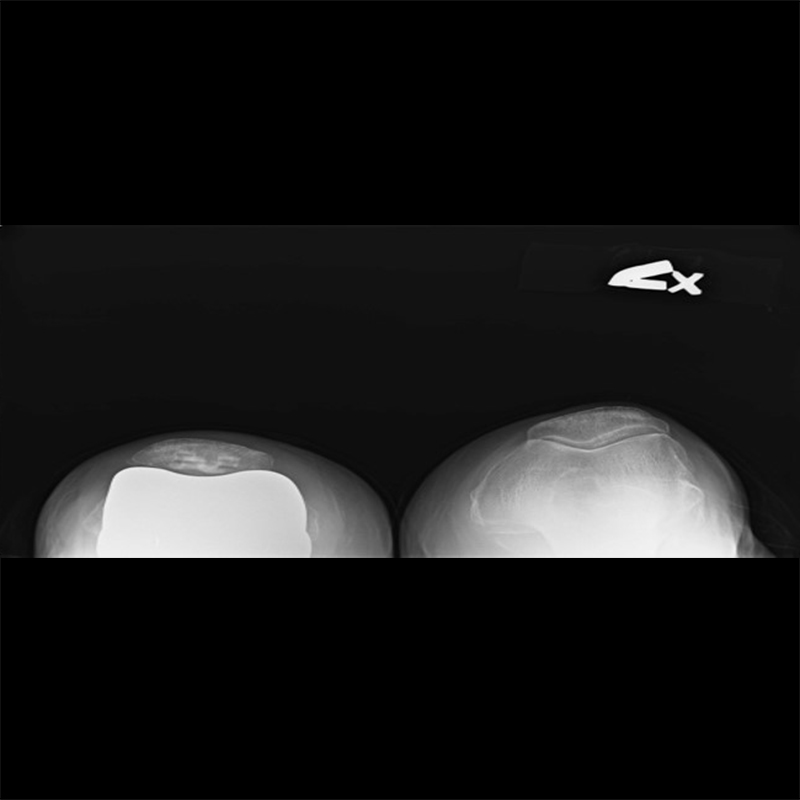

機器手臂手術 首頁 案例分享 膝關節手術 機器手臂手術 蔡女士 78歲 術前 術後 陳女士 70歲 術前 術後 術前 術後 ANGEVINE女士 73歲 術前 術後 U.S.A Mark 73歲 術前 術後 藍女士 78歲 術前 術後